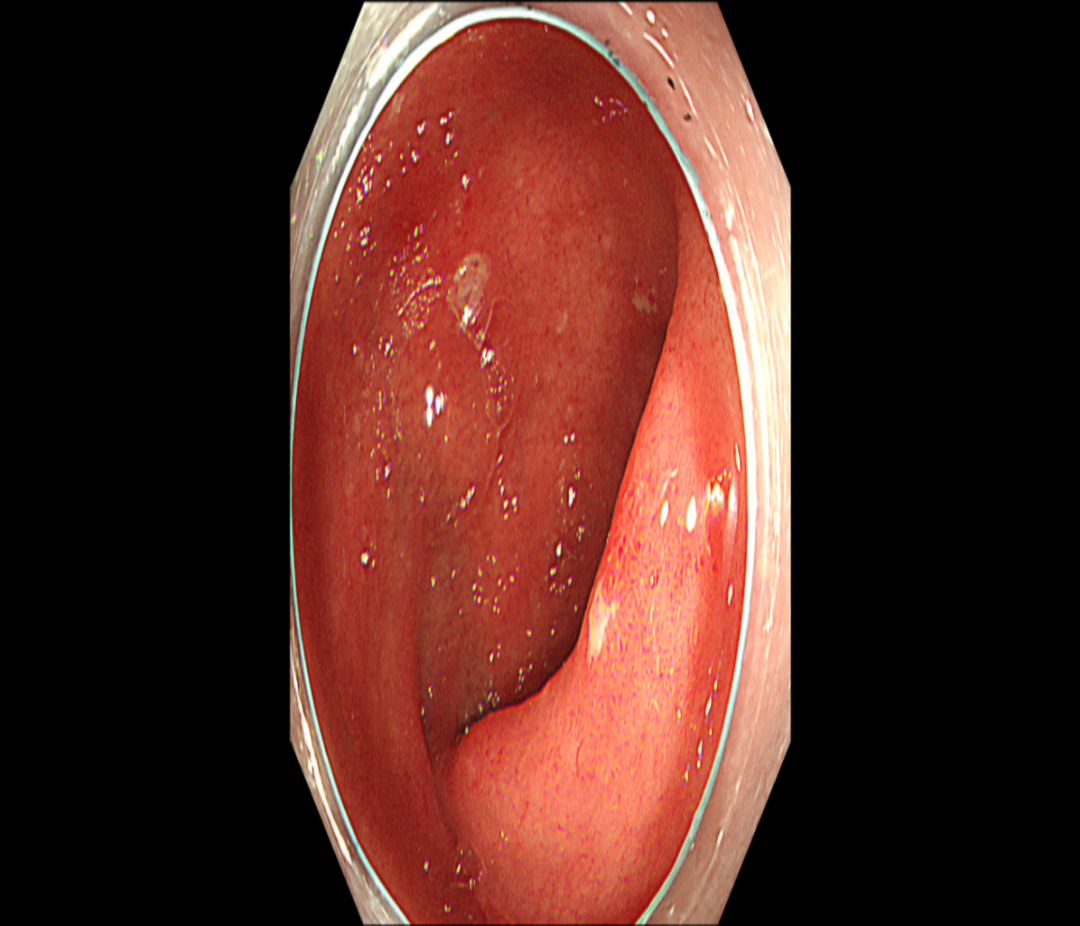

上腹部CT直接增强扫描(图2

1.肝多发囊肿。2.肠系膜周围多发淋巴结,部分肿大;肠系膜根部脂肪间隙稍欠清,考虑炎症性病变。

图2 上腹部CT直接增强示肠系膜周围多发淋巴结肿大、肠系膜根部脂肪间隙稍欠清